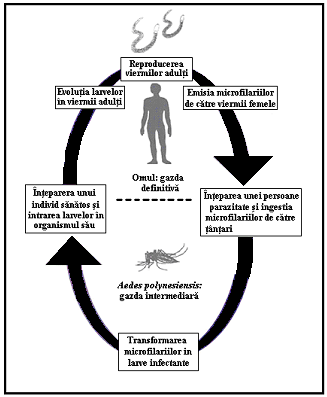

profound penetranteCiteste mai mult « 900 cuvinte, 2 pag. » Filarii

transmise de tabanide

Loaiaza (filarioza lui Guyot)

Infectia este endemica pentru Africa Centrala si de

Vest, in special in Angola, Camerun, Congo, Guineea Ecuatoriala, Gabon,

Nigeria, RCA, Zair.

Loa loa: Citeste mai mult « 1097 cuvinte, 3 pag. » Vaccinarea anti-papiloma